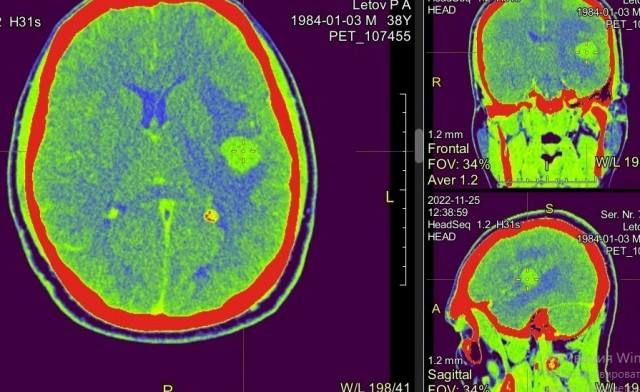

Сегодня был ошарашен новостью. Клиника в которой мне облучили в общей сложности шесть опухолей закрылась. В конце 2018 у меня обнаружили меланому. Операции, иммунотерапия, потом таргетная потом опять иммунная, и наконец в 2022 г. метастазы в мозг. Месяц адских болей, отëк мозга и не очень хорошие прогнозы. Но жена не особо хочет со мной прощаться, и вопреки прогнозам и советам врачей в нашем говнодрищенске без особых проблем находит и оформляет меня в клинику в Обнинске где мне делают облучение и я оживаю. Через три месяца у меня появляются ещё метастазы и я без труда опять попадают к этим золотым людям. Всё это по ОМС. Был я у них в мае 2023, после этого мне поменяли лечение и пока если не считать побочек, у меня всё хорошо. А сейчас я узнаю новость что клинику закрыли. И что делать если вдруг опять?

В 2018 году в Обнинске открылась Gamma Clinic, где установили аппарат гамма-нож — это радиохирургическая установка для лечения доброкачественных и злокачественных опухолей в полости черепа. Всего в России восемь таких аппаратов, но теперь станет на один меньше — 19 октября клиника закрылась по решению учредителей.

Центр принимал пациентов по ОМС. На лечение туда ехали со всей страны. Теперь людям с опухолями и метастазами в мозге будет непросто получить бесплатную медицинскую помощь — квоты на лечение гамма-ножом приходится ждать месяцами, а большинство таких клиник принимают онкобольных только платно.